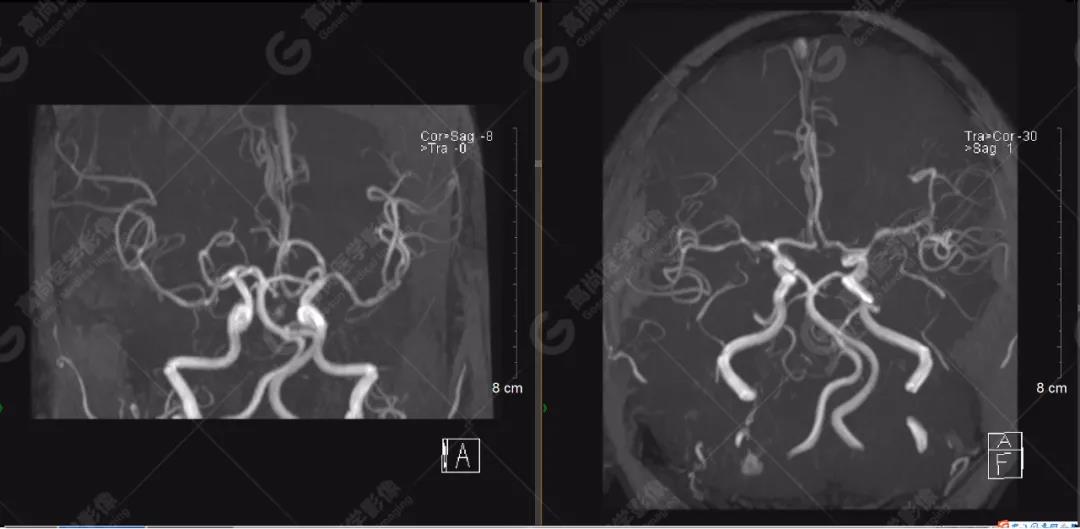

顱腦MRA及ciss序列示腦基底動脈環(huán)完整,雙側(cè)頸內(nèi)動脈末段、大腦前動脈、大腦中動脈、大腦后動脈及其主要分支顯影良好,管徑及走行正常,無明顯局灶性增粗或變細(xì)。雙側(cè)椎動脈末段沿延髓左側(cè)向上走行,左側(cè)面聽神經(jīng)輕度受壓移位,左側(cè)面聽神經(jīng)周圍見細(xì)小血管包繞。右側(cè)面聽神經(jīng)及雙側(cè)三叉神經(jīng)周圍未見異常血管影。

1.雙側(cè)椎動脈末段沿延髓左側(cè)向上走行,左側(cè)面聽神經(jīng)輕度受壓移位,左側(cè)面聽神經(jīng)周圍見細(xì)小血管包繞,可符合面聽神經(jīng)壓迫綜合征。